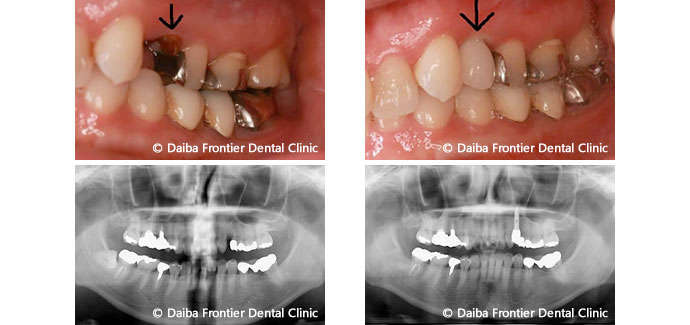

術前です。虫歯がひどく、残せないので抜歯が必要となりました。 -

抜歯と同時にインプラント手術を行います。抜歯部位には人工骨と、患者様自身から採血して遠心分離機によって抽出したフィブリンを使用し、再生療法を行う流れです。 -

オペ3ヶ月後。通常は抜歯後に時間が経つと骨が吸収され、無くなって凹んでしまいますが、抜歯と同時にインプラントオペをしたことにより骨の吸収もなく、綺麗に治癒しています。こちらのインプラントは埋まっている状態です。 -

抜歯前の術前の様子です。 -

インプラントをした箇所のセラミック治療後の画像です。 -

術後1年半後の様子です。骨の吸収も見られず、問題なく経過しています。